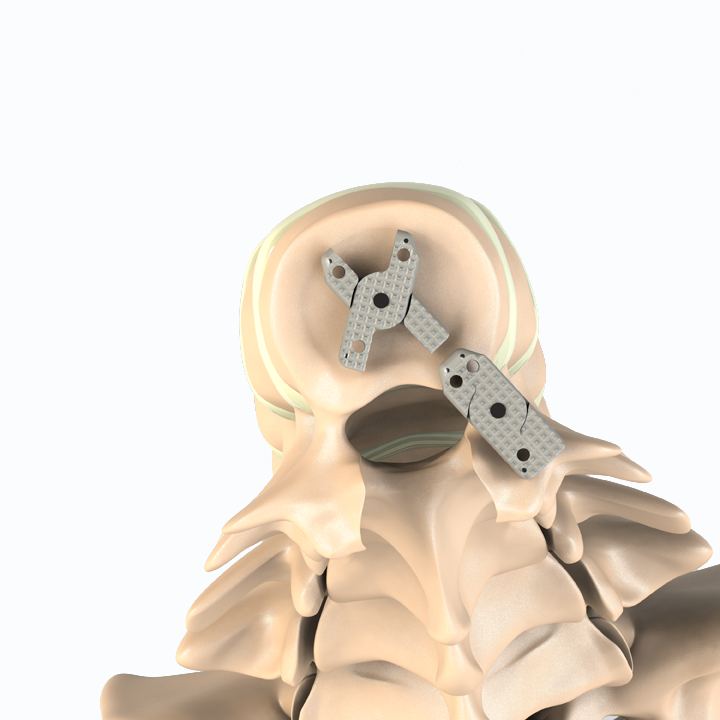

Aditus Lumbar Xlif Cage

- Anatomical Design

- Easy to Place within Disc Distance and Thanks to Elliptical Front Design

- Applicability of Posterior, Posterior Lateral or Extra Lateral from Disc Distance